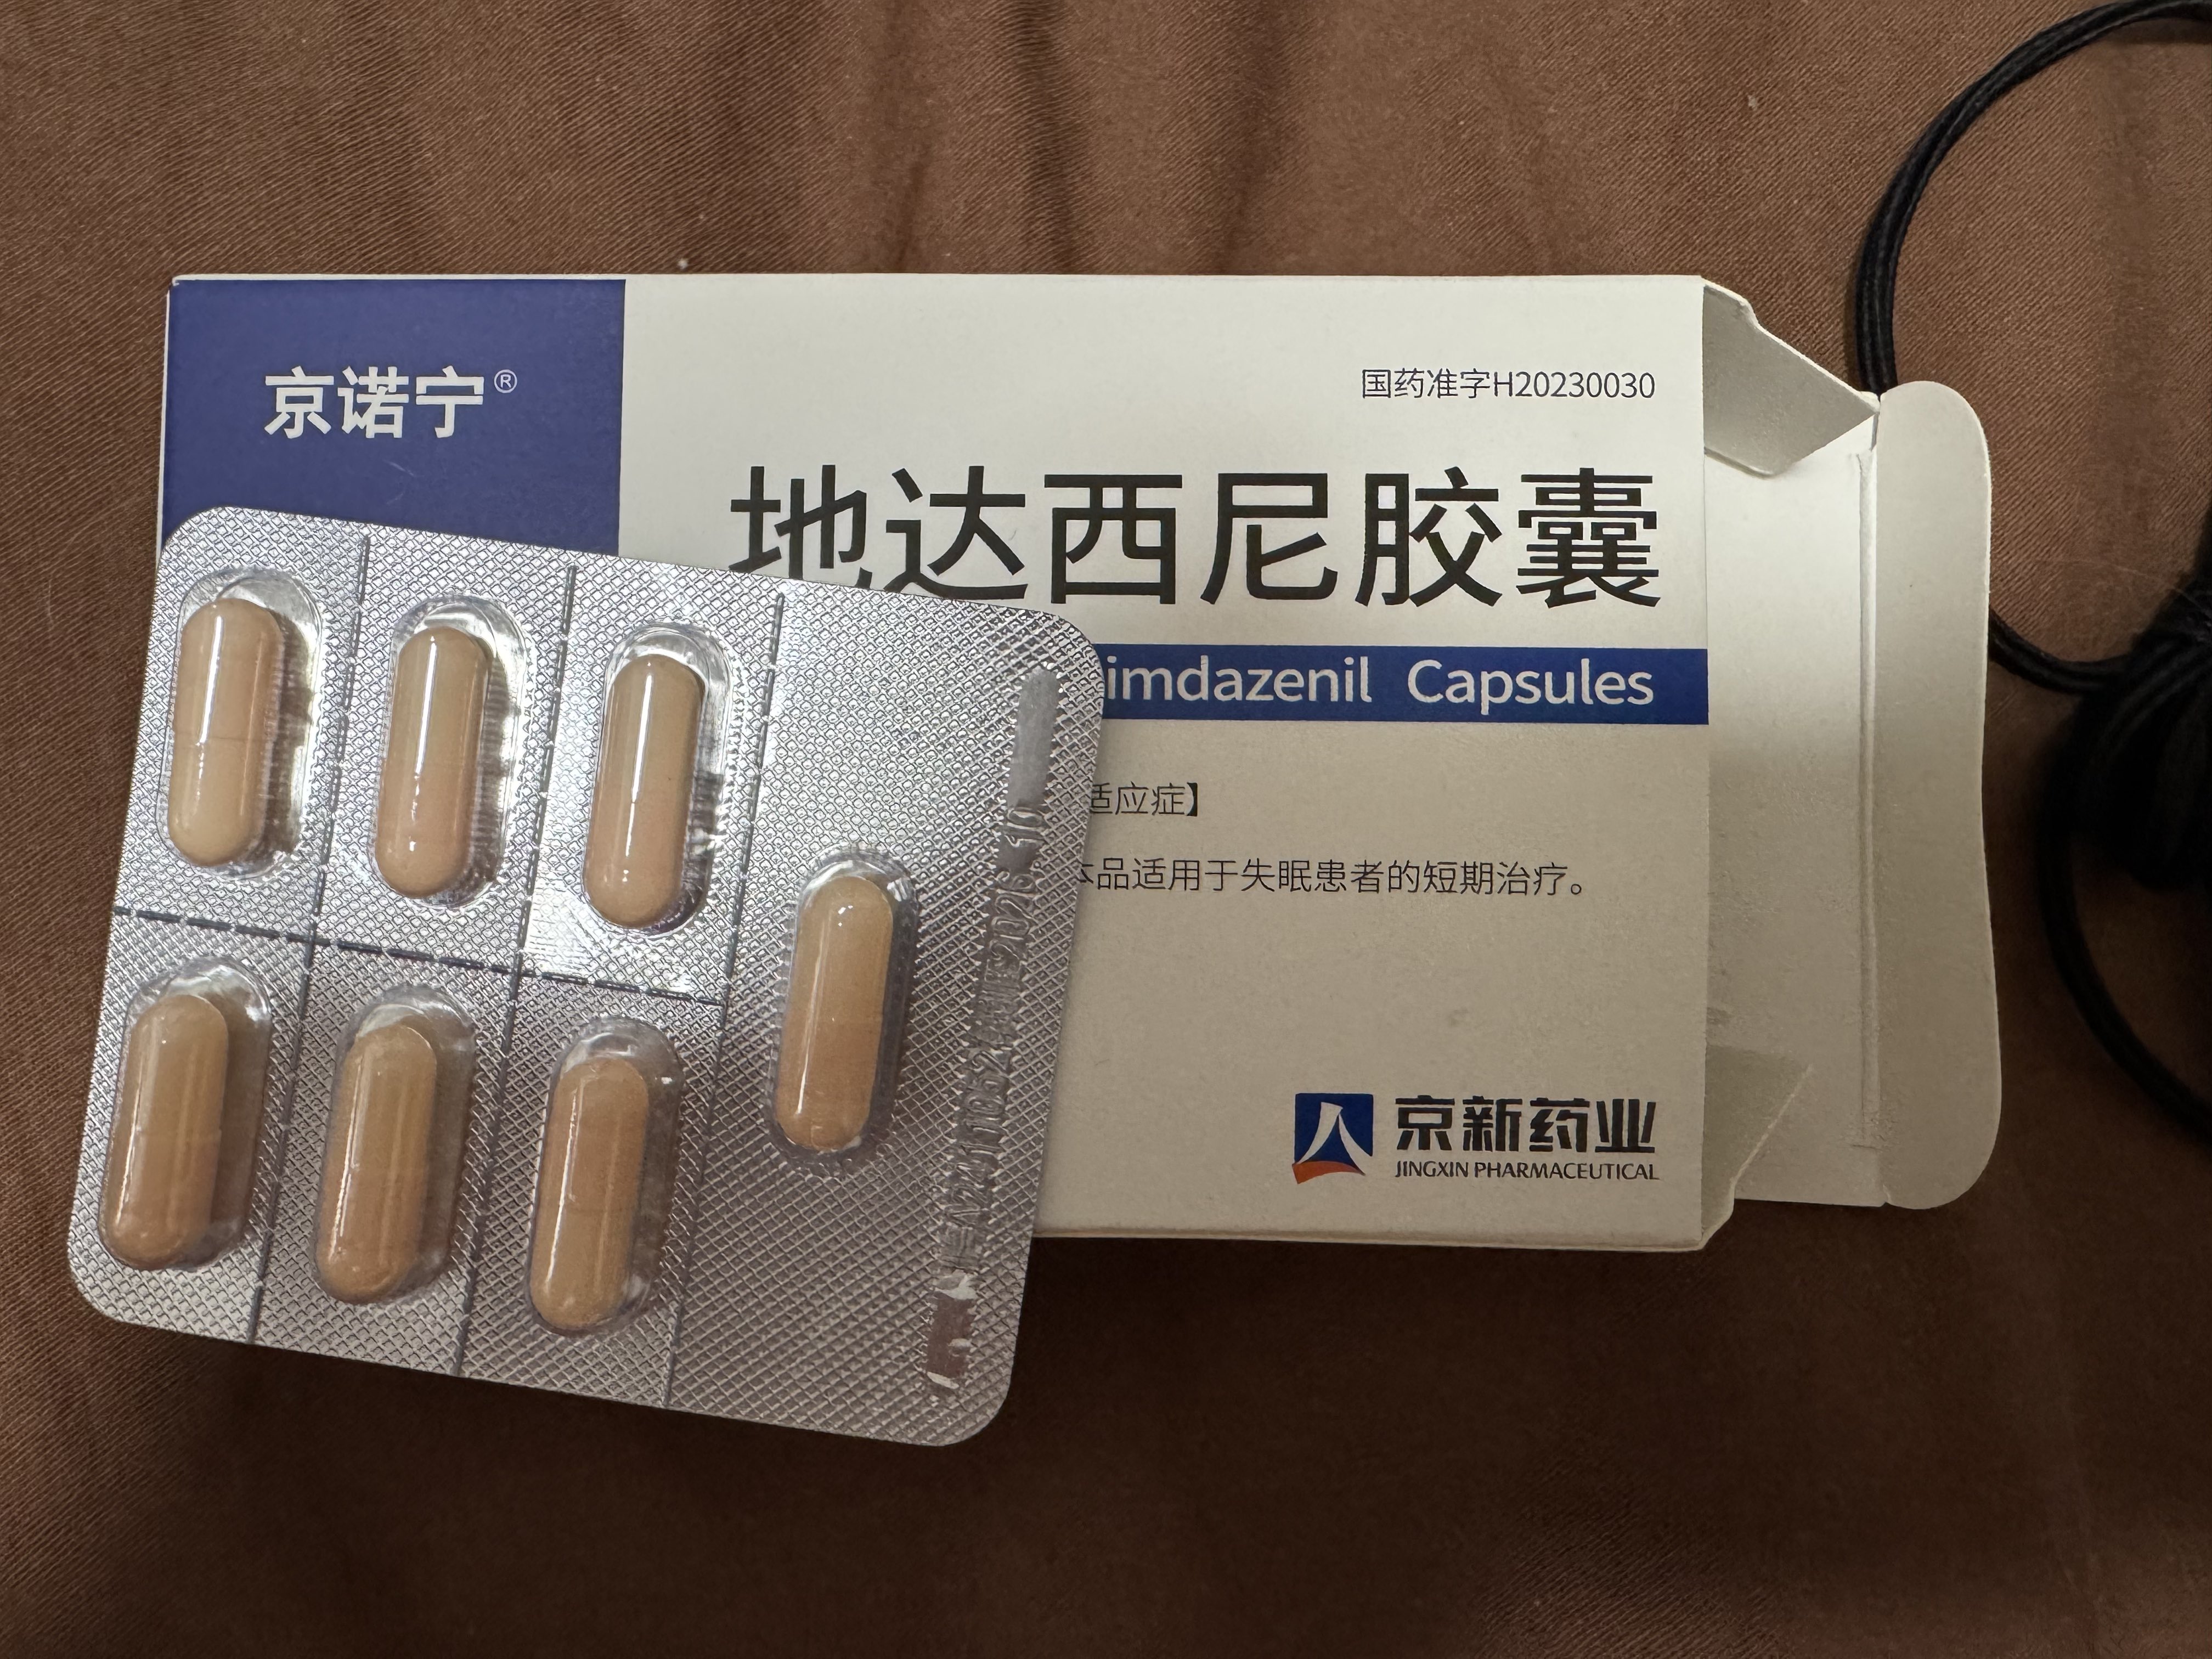

今天起来特别晕,完全不知道是怎么回事,以为是昨天测试物质的副作用我在想这么恐怖,然后怀疑今天是不是丁螺环酮吃了两次,直到我去看用药记录。。

好家伙唑吡坦又骗我吃药了还顺带上了个失忆状态,这下子知道是谁干的了。吃auv之后dxm清除得特别慢...让我感觉要从此告别了的程度,加上我基因检测本来cyp2d6就是中速代谢,这个尾巴就被拖的特别长